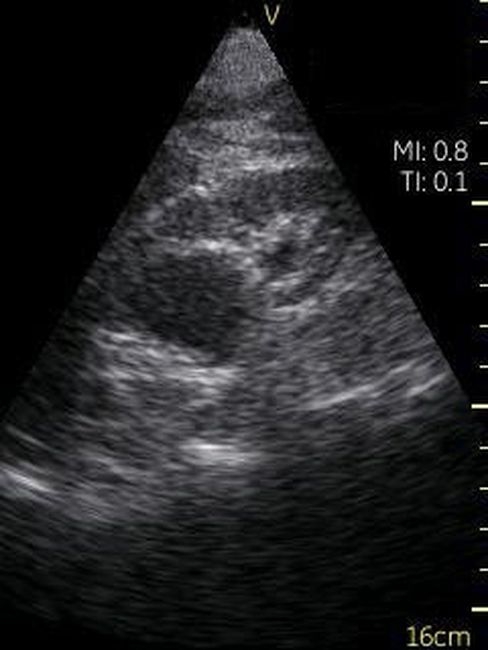

GE VSCAN – это УЗИ аппарат, реализованный в ультракомпактном корпусе, позволяющий делать черно-белые изображения тканей и органов реального времени. Ключевым отличием данного прибора от других моделей GE является его карманный размер, он чуть больше обычного смартфона. Идеальное средство для бригад скорой помощи, врача, принимающего пациента на дому, экстренной диагностики в полевых условиях.

Невозможно было представить раньше, что УЗИ аппарат может помещаться на ладони руки человека. Теперь это реальность, воплощенная в корпусе и технологической начинке GE VSCAN. Инженеры заложили возможность получения дополнительной визуализации кровотока с цветной кодировкой в режиме реального времени для полноценной постановки диагноза на месте.

Визуализация Vscan:

· Черно-белый режим для визуализации анатомических структур в реальном времени.

· Поле зрения в черно-белом режиме: до 75 градусов с максимальной глубиной 25 см.